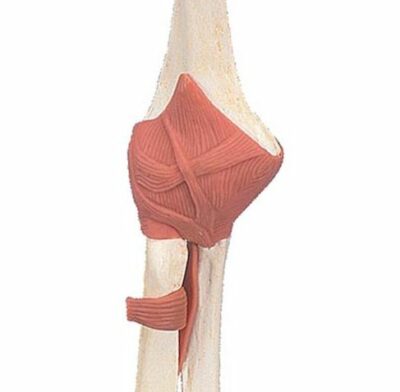

Modèle - Articulation fonctionnel du coude, Deluxe

Ce modèle fonctionnel de qualité supérieure d'une articulation droite avec ligaments grandeur nature montre l'anatomie et les possibilités de mouvements physiologiques dans une reproduction des détails unique. Monté sur socle.